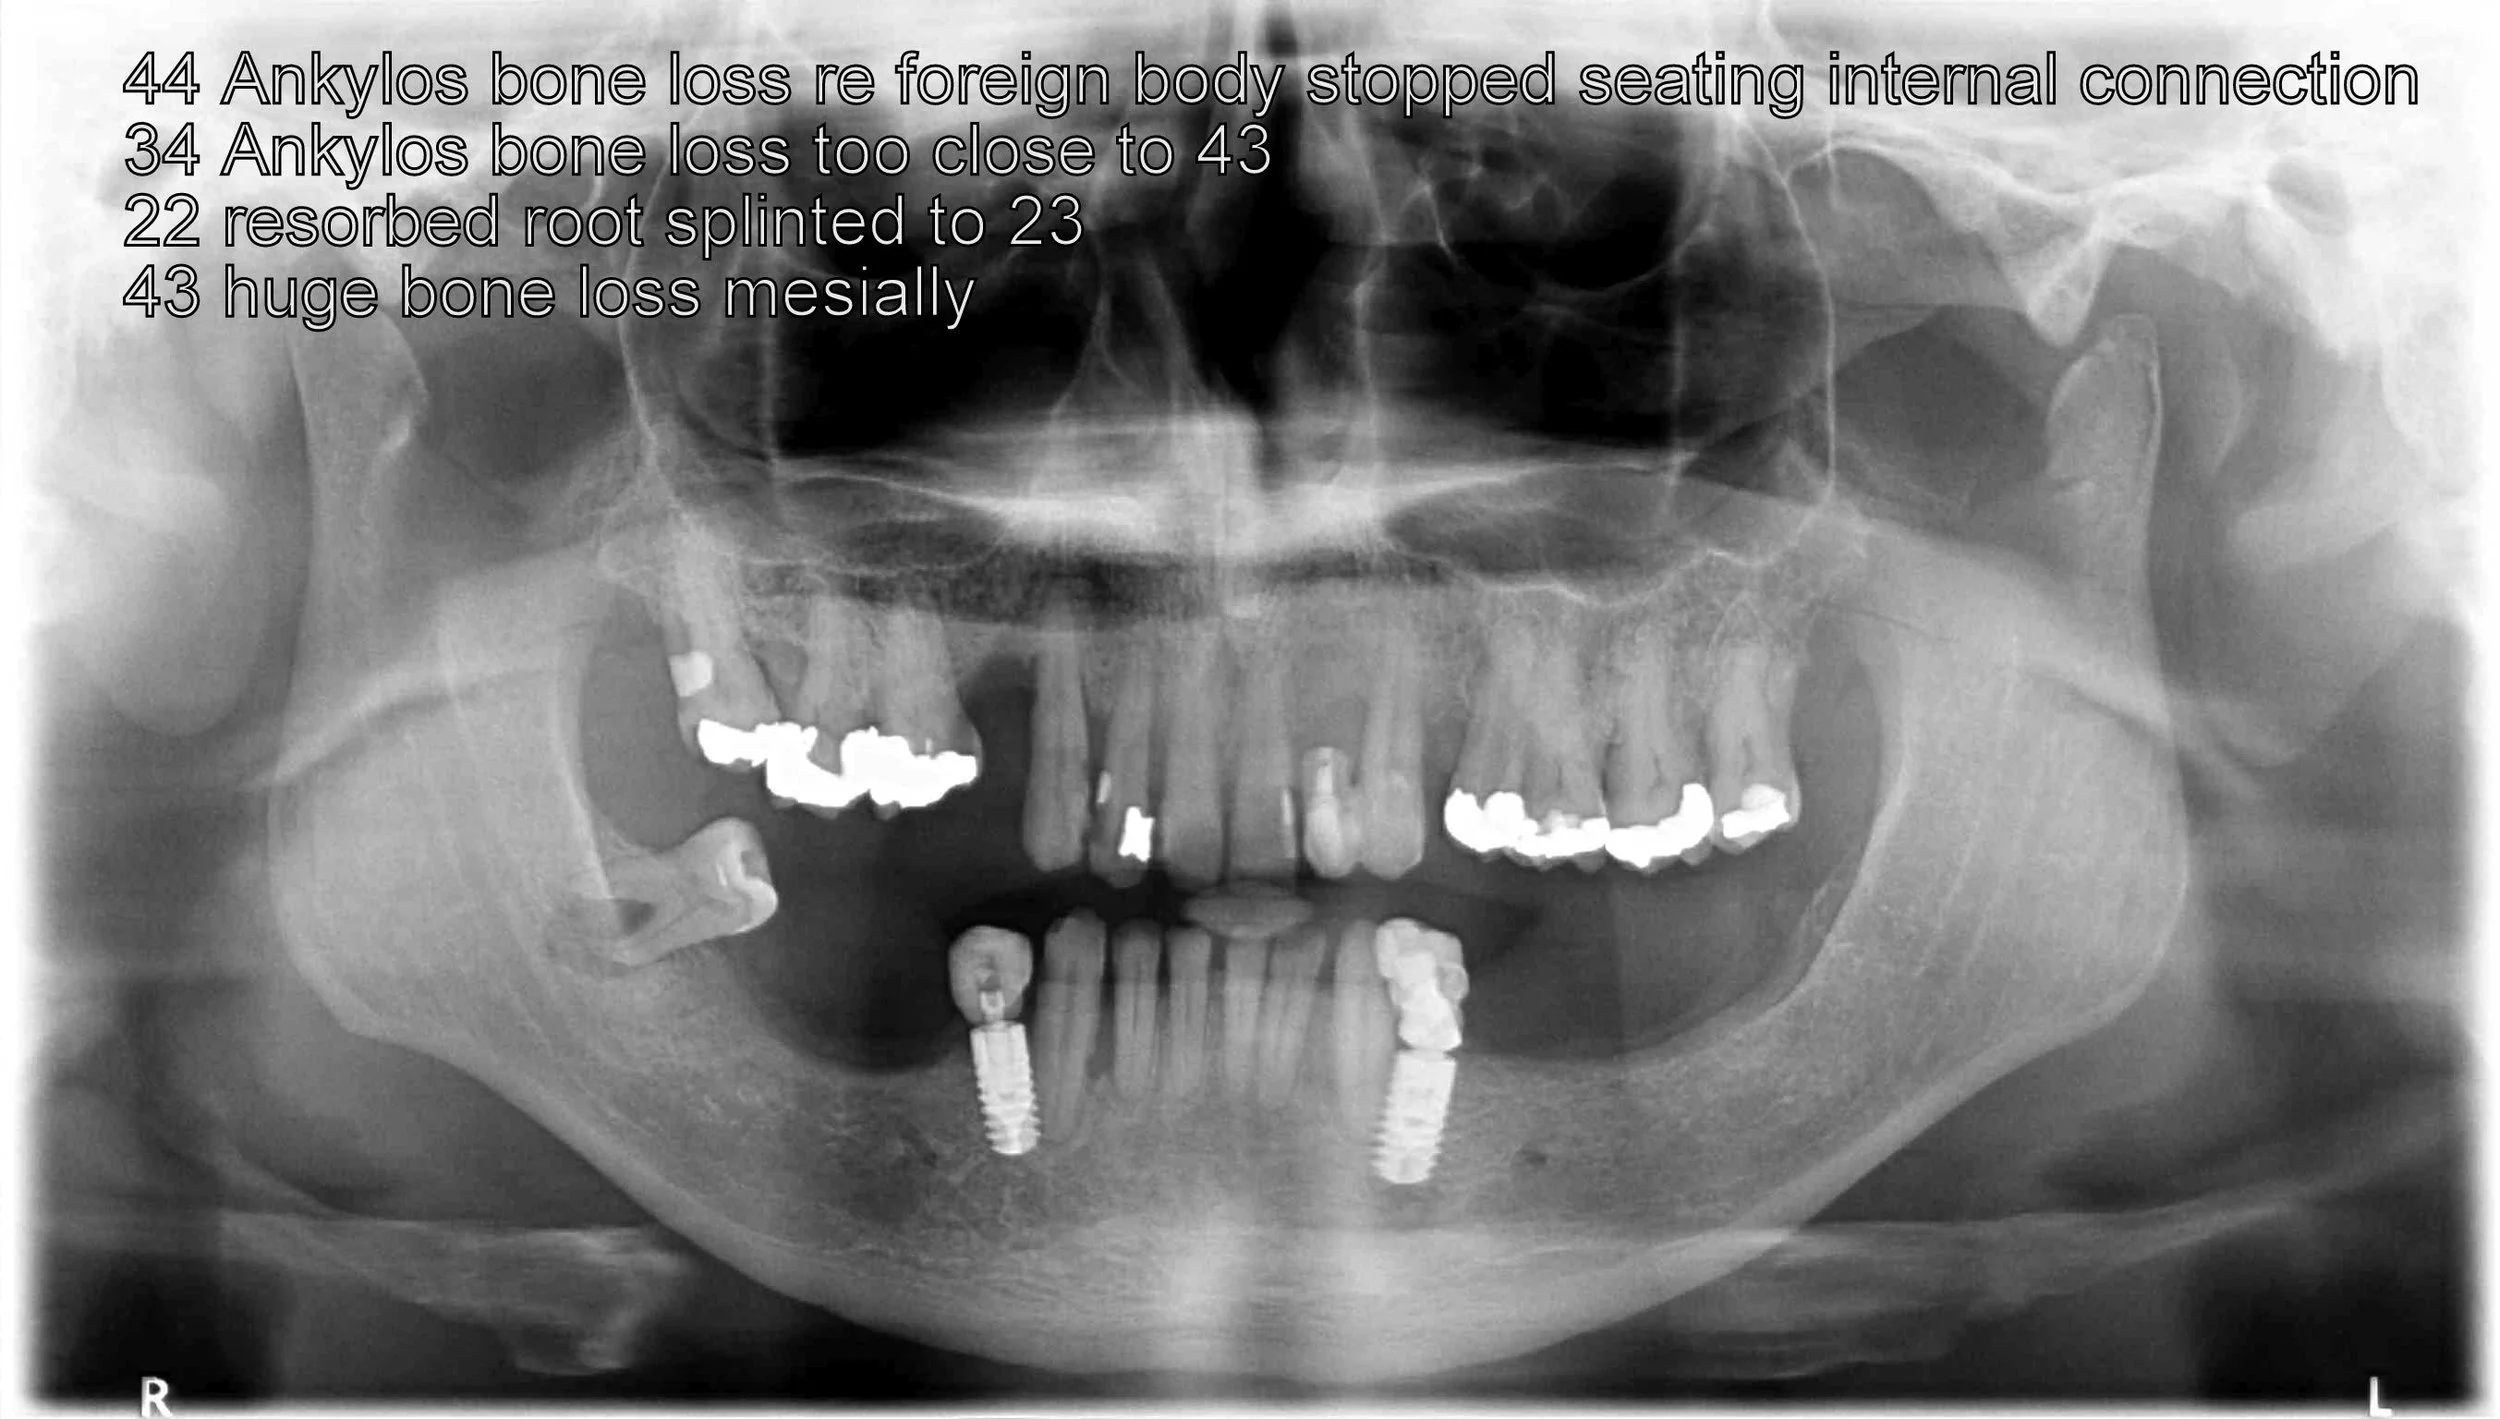

An OPG radiograph illustrating a variety of dental concerns and the presence of 2 implants in the lower jaw in the first premolar regions, namely, 34 and 44.

An OPG radiograph after the 6 extractions and Dr. Darveniza in 2014 surgically placed 2 Branemark implant fixtures between the existing 2 Ankylosis implant fixtures along with some artificial powdered RTR bone. Bone grafting adjacent to these Ankylosis implants was required following the extraction of the lower canines which had bone loss adjacent the 34 and 44 implant fixtures.